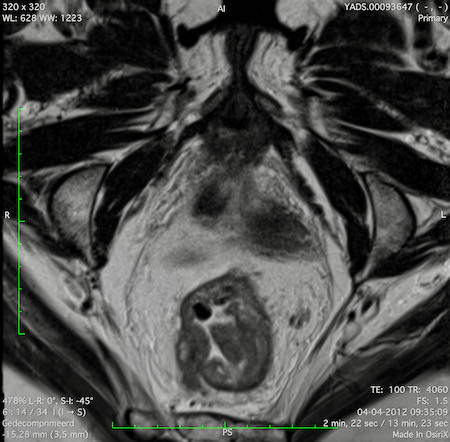

Hình ảnh

Các hình ảnh được cung cấp cho thấy ung thư biểu mô tế bào nhẫn với tình trạng dày lan tỏa thành trực tràng, hình ảnh bia bắn điển hình, và sự xâm lấn mỡ mạc treo trực tràng.